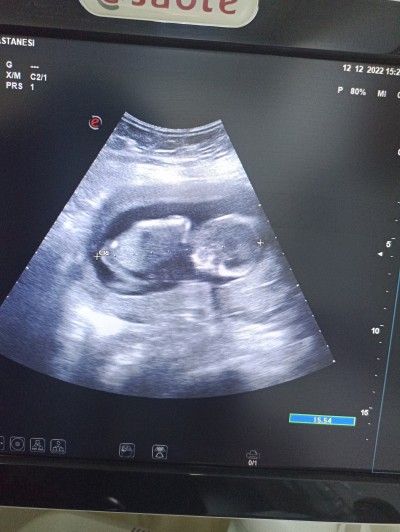

Arkadaşlar 16+6 haftalık hamileyim ama bebek bacaklarinı hicbi şekilde acmadı doktor erkeğe benzetti acaba tam olarak kacincı haftada öğrenebilirim böyle olup başına gelenler varmı sizin cinsiyetiniz ne acaba (:

image

Yedim girmed3n önce ama asla açmadı bacaklarıni

Aslnda çikolata felan yedim gormeden önce doktorda çok ugrastı salladı etti felan ama inatcı cıktı birazcık hayırlısı olsun bı oğlum var merakla beklicem